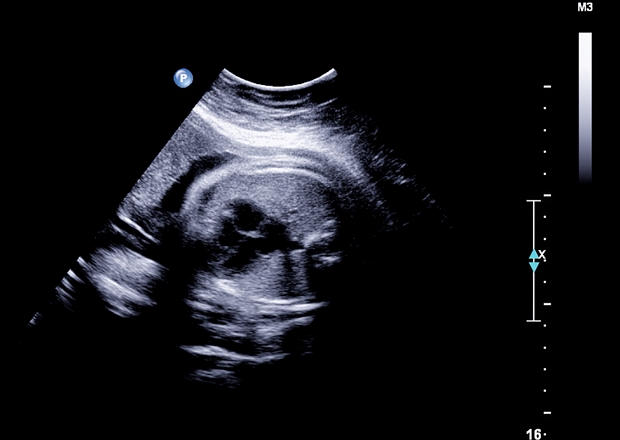

Az izraeli Weizmann Tudományos Intézet (WIS) kutatói legújabb vizsgálataik során megállapították, hogy az anya terhesség közbeni vírusfertőzése akár autizmust is előidézhet születendő gyermekénél. „Noha az autizmus első jelei általában csak 2-3 éves kor környékén jelentkeznek, mégis idegi-fejlődési rendellenességnek tekintjük, ami azt sugallja, hogy a változások már az agy embrionális fejlődése során elkezdhetnek kialakulni” - fejtette ki Orly Reiner, az intézmény professzora. A kutatók vemhes egerek esetében szimuláltak vírusfertőzést, és a kísérlet rendkívül értékes konklúziókkal gazdagította őket.